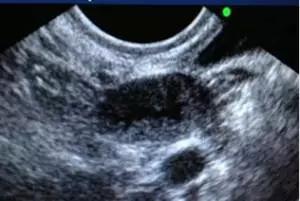

进入IVF周期后,在月经周期第2~3天,需至生殖中心行基础超声检查,通过测量双侧卵巢内窦卵泡的大小及个数,评估本周期卵巢的基础状态,以确定促排卵的方案及药物剂量。如果有优势卵泡提前出现者,根据患者的个体情况,制定下一步治疗方案。

在启动促排卵药物4~5天后,需要再次行超声监测,观察双侧卵巢内生长卵泡的发育情况,包括优势卵泡大小、数目、子宫内膜厚度、及盆腔情况,进行药物的调整,可能包括:(1)调整或维持促排卵药物的剂量,预约下次超声监测的时间;(2)如果出现意外或不利情况,则取消或终止本周期的治疗。

此后随着优势卵泡逐渐增大,卵泡的超声监测相对更加频繁,直至卵泡发育成熟,到达HCG扳机标准,一般共约3~5次卵泡监测,注射后36~37小时在阴道超声进行取卵术。